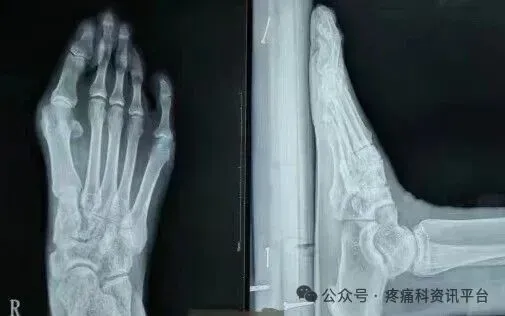

原石家庄市三院副院长冯建书亲自讲课示教,患者身边近距离看手术,可随时提问。冯建书:原石家庄第三医院(石家庄市骨科医院)副院长 手足外科主任可开发票,会后由承办单位石家庄君臣佐使会议服务有限公司提供会务费发票.图为术前术后对比图

本次培训以“理论+临床观摩+学员亲自动手截骨(动物标本)"为主,三位一体全面掌握这项技术。在上午理论授课环节,冯主任亲授临床经验和技巧,共同分享多年临床经验和研究心得,让大家在学习中相互交流,在实践中共同进步。培训间隙,老师会教大家术后包扎要领、手术松解等内容下午安排进手术室观摩,老师边手术边讲解在术中需要注意的地方,通过近距离的观摩深入掌握了解这项技术